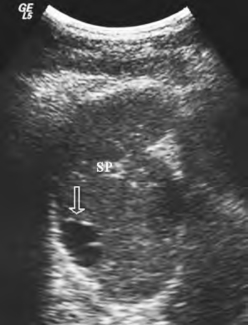

1.脾实质内见圆形、椭圆形无回声区,单个,较大,囊壁光滑,囊后方回声增强(图24-2)。

图24-2 脾脏囊肿声像图

箭头示囊肿。SP:脾脏